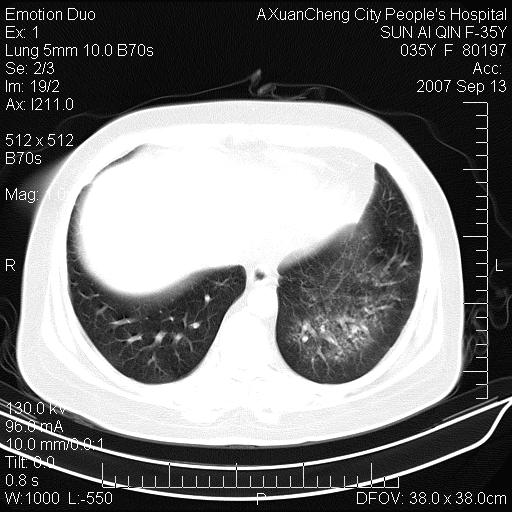

以下是引用天南地北在2007-9-13 13:43:00的发言:[br]考虑双肺、肺门侵润

以下是引用ydx_74在2007-9-13 15:42:00的发言:[br]仅看片,考虑右上肺癌并双肺转移,结合病史,考虑肺门、肺内淋巴侵润

以下是引用同在2007-9-13 15:08:00的发言:[br]支持肺门及双肺侵润.